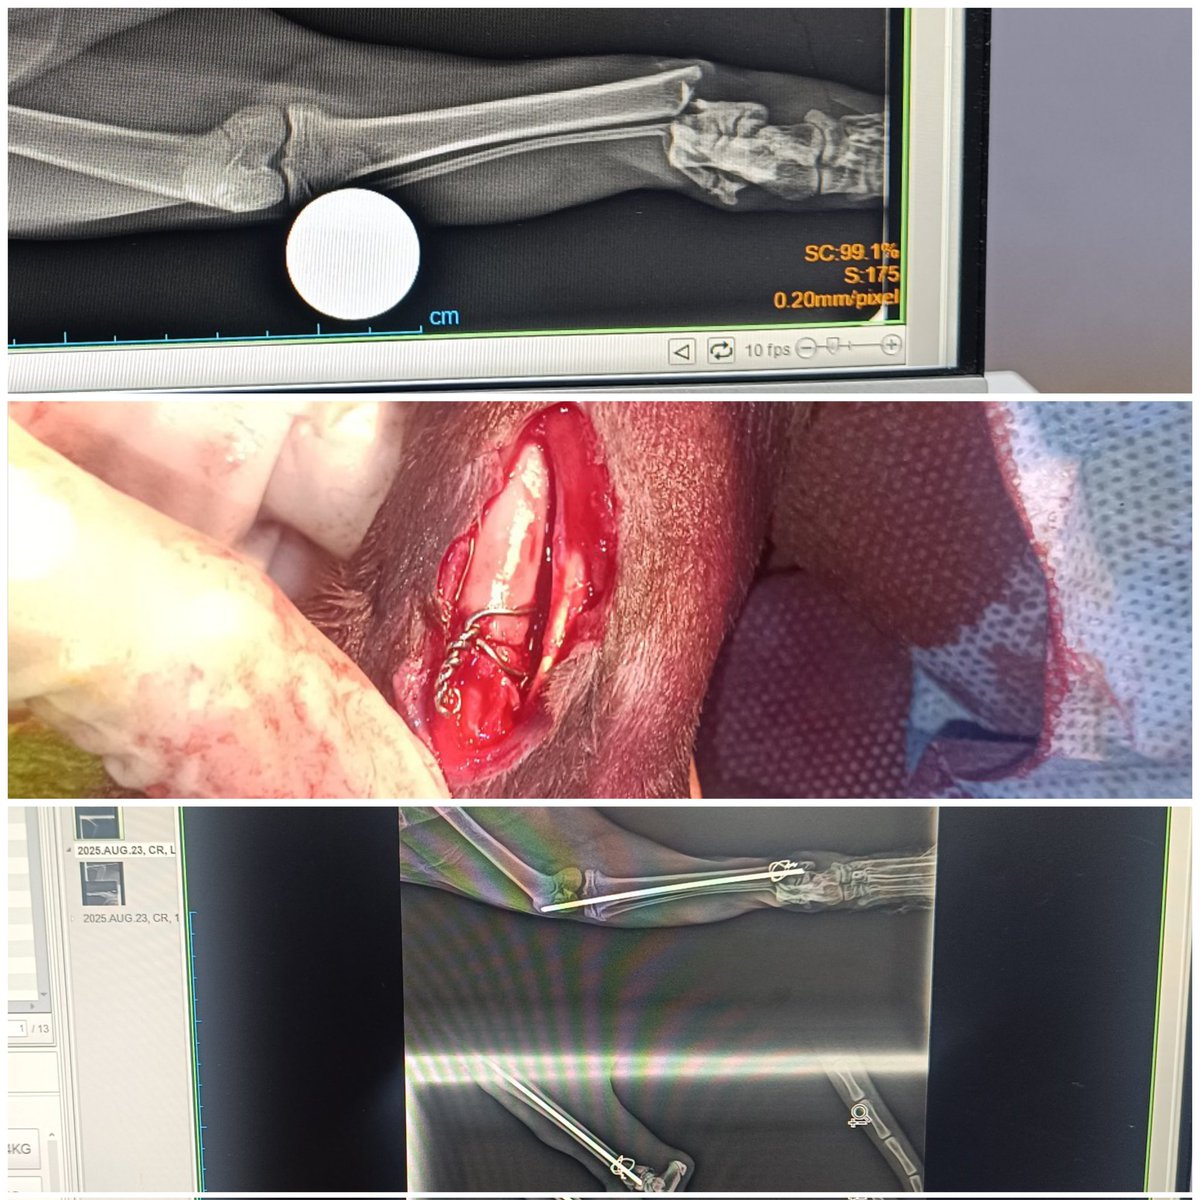

Bugünkü vakamız: tibia-fibula fraktürü 🦴 Operasyon öncesi ve sonrası farkı görmek bile insanı mutlu ediyor 🙏 Intramedüller pin + cerclage telleri ile başarılı bir şekilde stabilize ettik. Minik dostumuzun kısa sürede sağlığına kavuşması için süreci yakından takip ediyoruz 🐾❤️

Bugünkü vakamız: tibia-fibula fraktürü 🦴

Operasyon öncesi ve sonrası farkı görmek bile insanı mutlu ediyor 🙏

Intramedüller pin + cerclage telleri ile başarılı bir şekilde stabilize ettik.

Minik dostumuzun kısa sürede sağlığına kavuşması için süreci yakından takip ediyoruz 🐾❤️